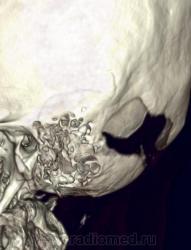

Nela. КТ головного мозга и костей. Гистиоцитоз Х (морфологическая верификация).

Пациент - молодой человек, предъявляет жалобы на головные боли и боли в шее. Болеет с 2002 года.

Гистиоцитоз Х – заболевание ретикулоцитарной системы неизвестной этиологии, морфологически характеризующееся первичной пролиферацией своеобразных гистиоцитов (клеток Лангерганса или клеток Х) и образованием в легких и в других органах и тканях гистиоцитарных гранулем и гранулематозных инфильтратов.

В понятие “гистиоцитоз Х” включают болезнь Abt–Letter–Siwe, болезнь Hand–Schuller–Christian, а также эозинофильную гранулему с разной степенью выраженности гистиоцитарной пролиферации.

Заболевание относится к системным: гранулемы могут образовываться в различных органах, но наиболее часто поражаются легкие и кости. Заболевают чаще всего люди молодого возраста, между 20 и 40 годами, большей частьюмужчины.

Частота гистиоцитоза Х составляет в среднем 5 на 1 000 000 человек. Более 90% заболевших курильщики.